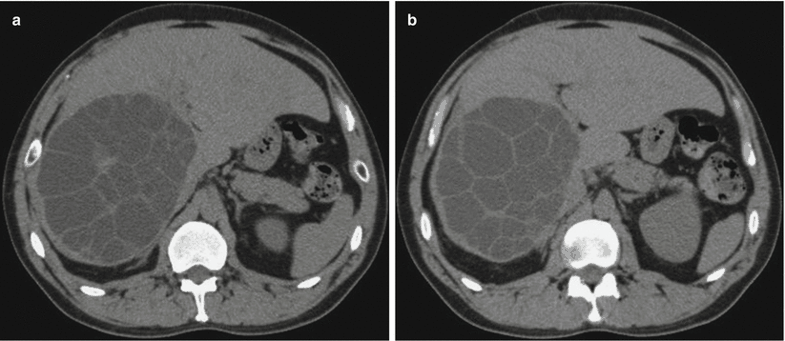

Daughter cysts

Echinococcal cyst within a larger cyst

Can occur in liver or spleen